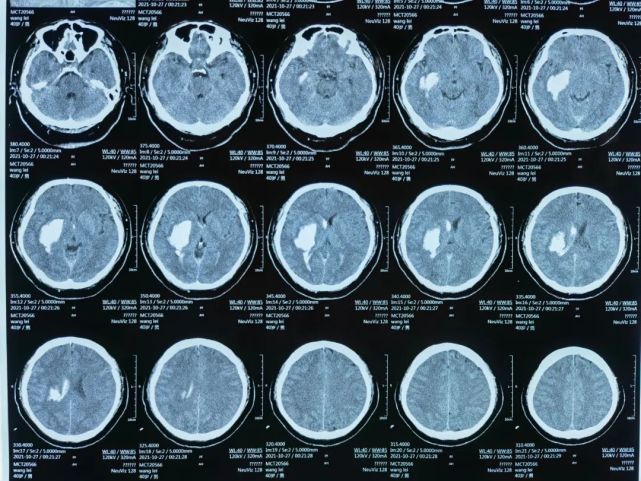

基底节出血ct图片

左侧基底节区脑出血破入双侧脑室

第二次ct(24时)示右侧基底节区脑出血量约40ml且破入脑室

赵建和,男,59岁,右侧基底节区出血破入脑室

闫聪,女,16岁,右侧基底节出血破入脑室

史力,男,65岁,右侧基底节区出血破入脑室蛛网膜下腔